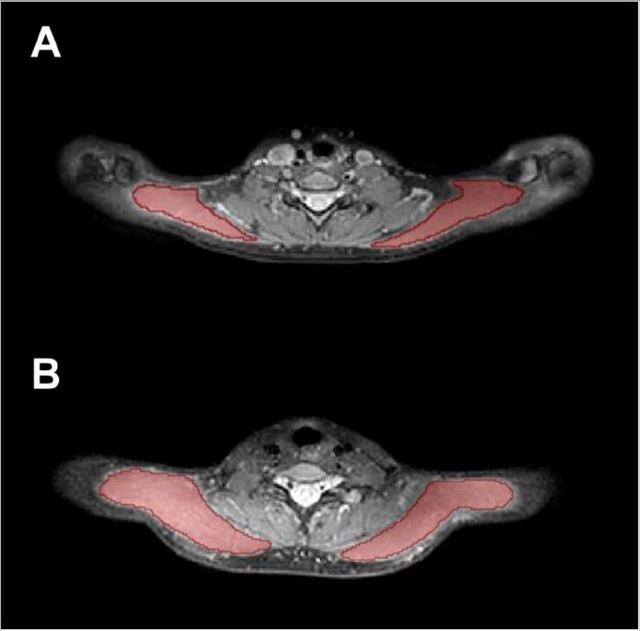

At 7 tesla, translational and rotational forces on metallic implants, devices, and foreign bodies are pronounced, and the risks of tissue and implant heating are higher due to shorter RF wavelengths and higher specific absorption rate (SAR).

"Slowing down the rate at which patients are moved through the static field gradient may help mitigate symptoms like vertigo and dizziness," the researchers pointed out. "Monitoring RF-related heating in tissue at 7 tesla poses unique challenges due to the lack of a single-channel body RF transmit coil, unlike 1.5- and 3-tesla MRI systems."